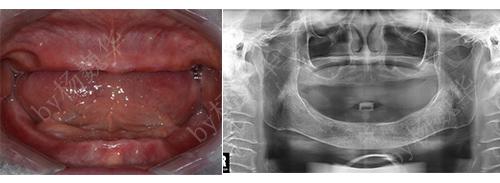

性别:女

年龄:68

主治医生:杨登

所在门诊:宁德中富口腔

主诉:下颌活动牙松动,咨询种植牙修复

治疗方案:下颌种植覆盖义齿修复(后来转为种植牙固定修复)

术前